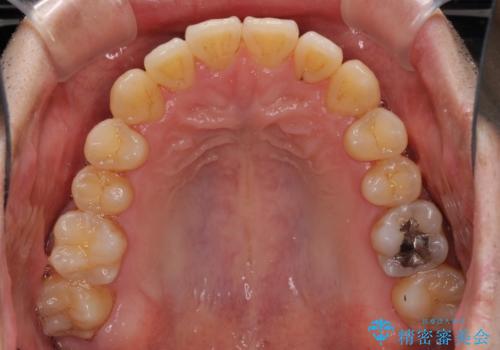

- 上下の前歯の反対咬合を気にして来院された患者様です。

インビザラインを用い、下顎はIPR(歯と歯の間を削る)と歯列全体を後方に移動させ、上顎は前歯を持ち上げることで、反対咬合を改善していくこととしました。

八重歯の歯根が見えている点も気になっているので、矯正歯科治療後に歯肉移植による根面被覆を行うこととしました。

インビザラインによる反対咬合の改善は、上の歯が下の歯を乗り越えていく期間に咬み合わせが非常に不安定となり、治療が長期化することがあります。

また、ワイヤー矯正と異なり歯軸改善の強い力を前歯にかけるため、反対咬合で裏側にある歯の歯肉が退縮しやすくなります。

矯正治療により元々気になっていた八重歯と、反対咬合が改善された歯の2本に対して根面被覆を行い、審美面の改善も達成しました。